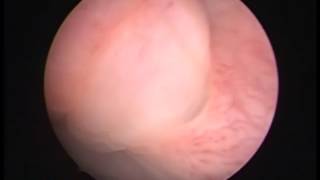

TURis Plasma Vaporization εξάχνωση προστάτη Δρ. Κυμηνάς Laser λιθοθρυψία με εύκαμπτο ουρηρτηροσκόπιο Εξελκυσμός λίθου ουρητήρα Διουρηθρική όγκου ουροδόχου κύστεως 1 www.kyminas-urology.gr Διουρηθρική προστατεκτομή TURis Δρ. Κυμηνάς Ευάγγελος www.kyminas-urology.gr TUR-P Διουρηθρική προστατεκτομή TURis 1 Δρ. Κυμηνάς Ευάγγελος www.kyminas-urology.gr Laser λιθοθρυψία λίθου ουρητήρα Δρ. Κυμηνάς Ευάγγελος www.kyminas-urology.gr ουρητηροσκόπηση καρκίνος ουρητήρα Δρ. Κυμηνάς Ευάγγελος www.kyminas-urology.gr Ουρητηροκήλη Δρ. Κυμηνάς Ευάγγελος www.kyminas-urology.gr Διουρηθρική θηλώματος κύστεως υψηλού βαθμού κακοήθειας Kyminas-urology.gr